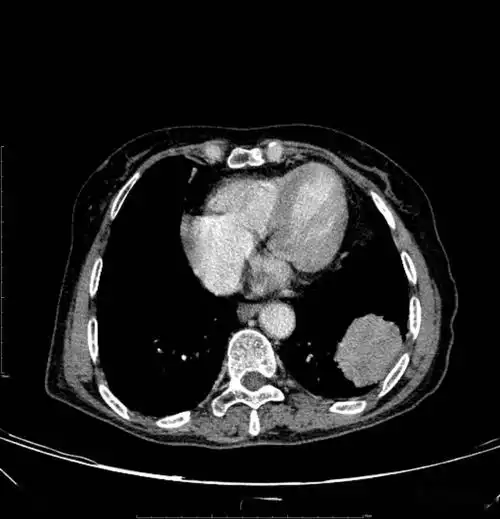

图片是患者ct平扫和多期增强扫描(动脉期,静脉期,平衡期或延迟期)的